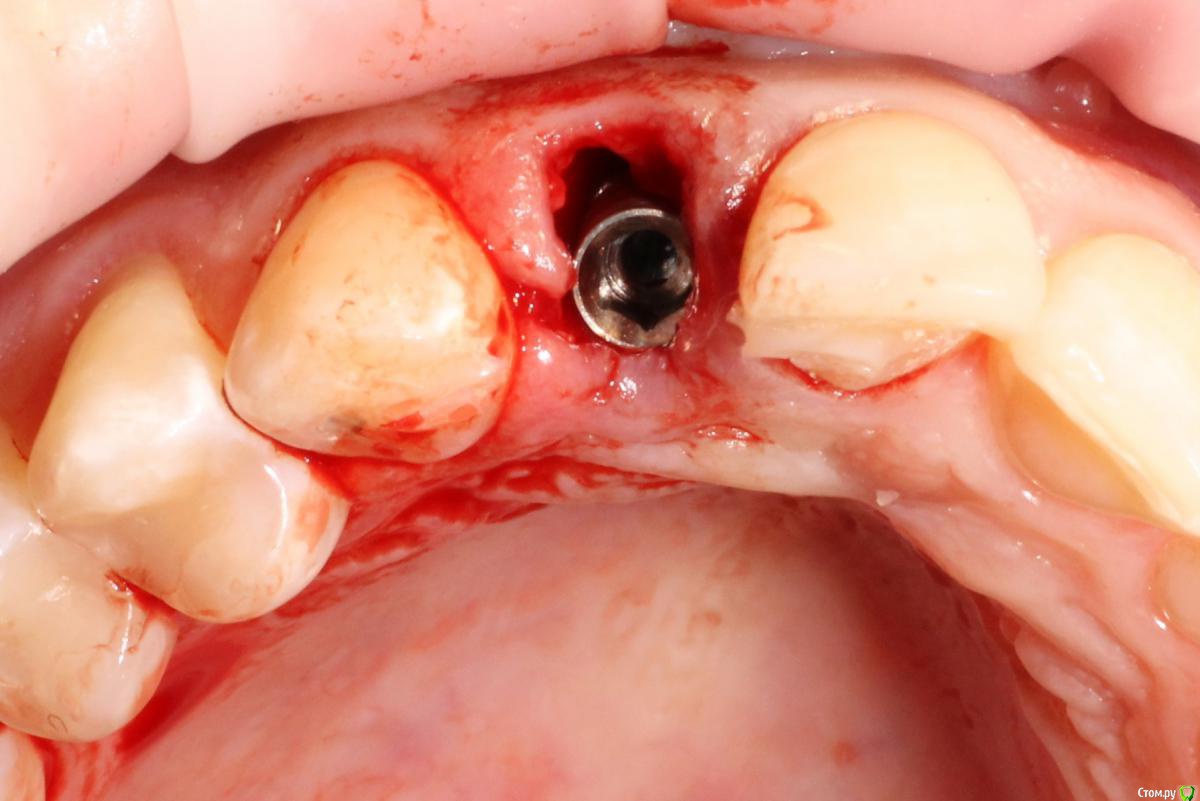

MenshikovDV Опубликовано 2 апреля, 2015 Поделиться Опубликовано 2 апреля, 2015 (изменено) Зуб 1.2 отлом коронковой части зуба, на период ожидания приема у хирурга и ортопеда (2 дня) приклеен к соседям. Вся процедура в одно посещение. Где-то часа два. Я ортопед, хирургия не моя, фото мои Изменено 2 апреля, 2015 пользователем MenshikovDV 19 Ссылка на комментарий

an_ver Опубликовано 2 апреля, 2015 Поделиться Опубликовано 2 апреля, 2015 SPI? В лунку что нибудь кидали во время установки? Ссылка на комментарий

MenshikovDV Опубликовано 2 апреля, 2015 Автор Поделиться Опубликовано 2 апреля, 2015 Нет, ничего не кидали. Ссылка на комментарий

Lolopop Опубликовано 3 апреля, 2015 Поделиться Опубликовано 3 апреля, 2015 альфабио?)))какой торк получили? Ссылка на комментарий

АнтонТЛТ Опубликовано 4 апреля, 2015 Поделиться Опубликовано 4 апреля, 2015 Судя по фото Alpha bio SPI, торк около 40 Ссылка на комментарий

MenshikovDV Опубликовано 5 апреля, 2015 Автор Поделиться Опубликовано 5 апреля, 2015 торк намного больше 40 Ссылка на комментарий